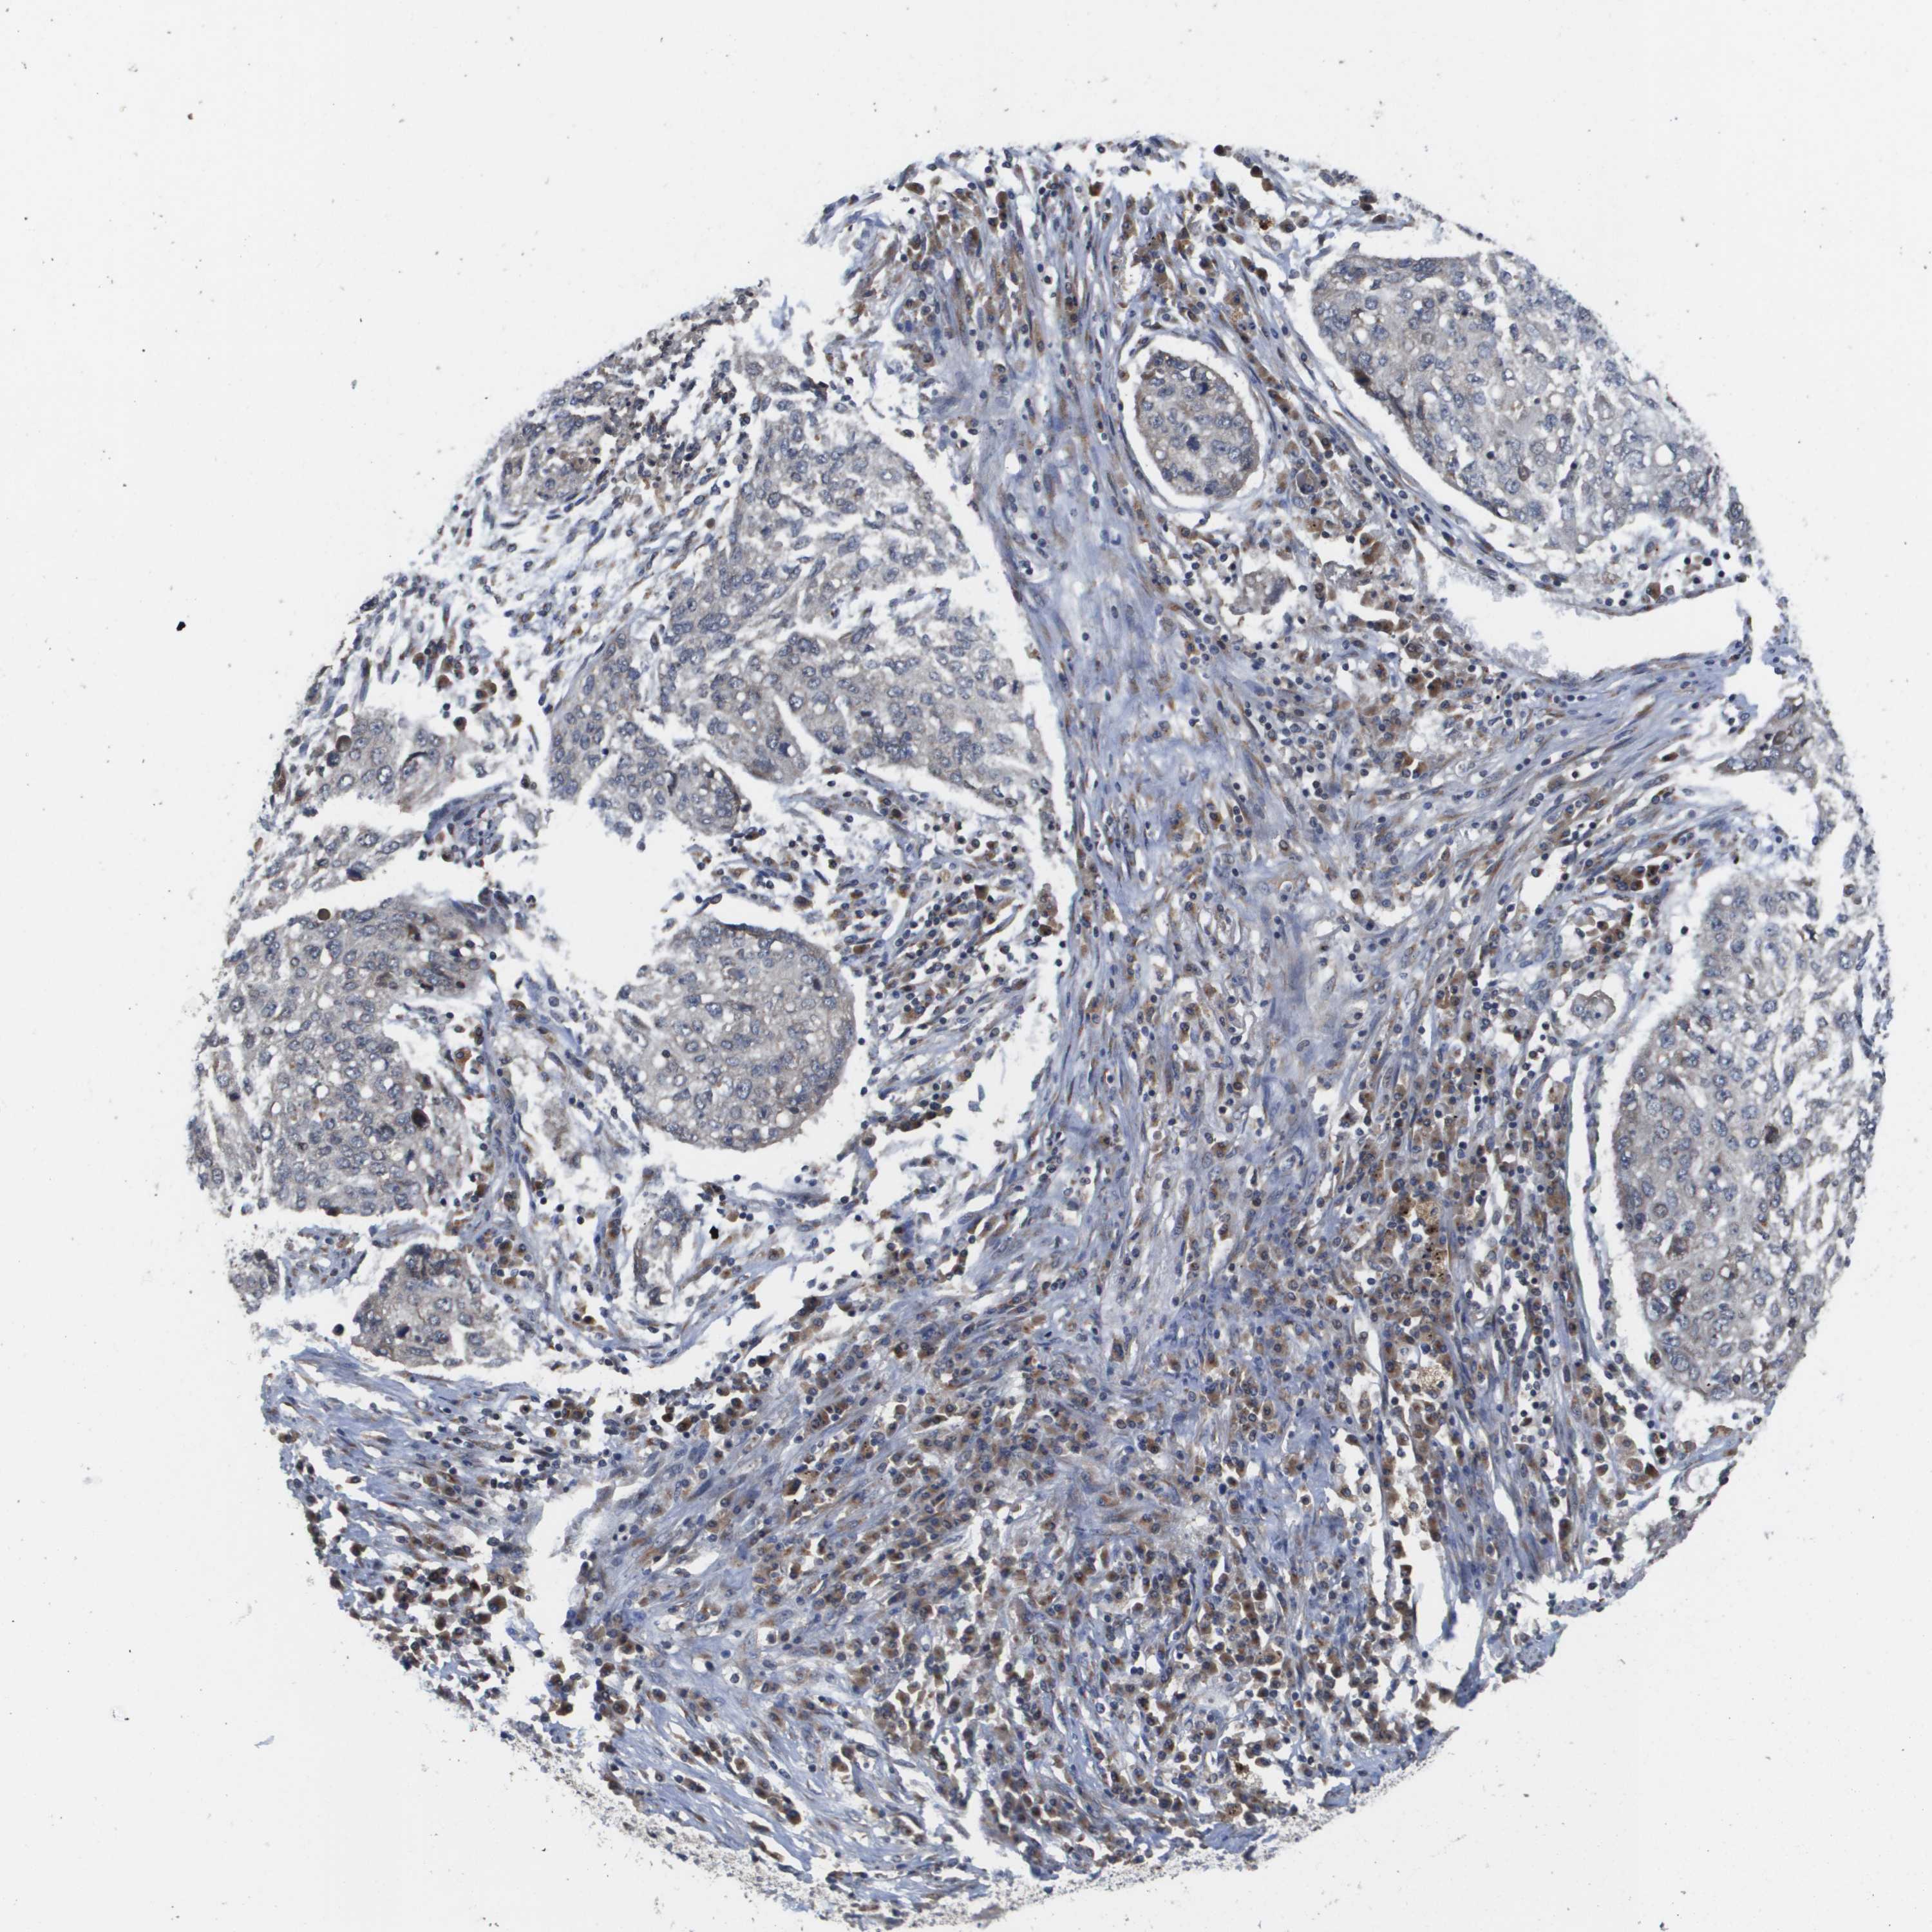

LUNG ADENOCARCINOMA (VALIDATION) - Interactive survival scatter ploti

The Survival Scatter plot shows the clinical status (i.e. dead or alive) for all individuals in the patient cohort, based on the same data that underlies the corresponding Kaplan-Meier plots. Patients that are alive at last time for follow-up are shown in blue and patients who have died during the study are shown in red.

The x-axis shows the expression levels (FPKM) of the investigated gene in the tumor tissue at the time of diagnosis. The y-axis shows the follow-up time after diagnosis (years). Both axes are complimented with kernel density curves demonstrating the data density over the axes. The top density plot shows the expression levels (FPKM) distribution among dead (red) and alive patients (blue). The right density plot shows the data density of the survived years of dead patients with high and low expression levels respectively, stratified using the cutoff indicated by the vertical dashed line through the Survival Scatter plot. This cutoff is automatically defined based on the FPKM cutoff that minimizes the p-score. The cutoff can be changed by dragging the vertical line or by entering a cutoff value in the square labeled "Current cut-off".

Under the Survival Scatter plot the p-score landscape (black curve; left axis) is shown together with dead median separation (red curve; right axis). Dead median separation is the difference in median mRNA expression between patients who have died with high and low expression, respectively. It is calculated as follows: median FPKM expression of dead patients with high expression - median FPKM expression of dead patients with low expression. This is intended to aid the user in visually exploring custom cutoffs and the associated p-scores and dead median separation.

Individual patient data is displayed and can be filtered by clicking on one or more of the category buttons on the top of the page. Categories describing expression level and patient information include: high, low, alive, dead, female, male and tumor stages. The scale of the x-axis can be toggled between linear and log-scale by clicking on the "x log" button. Mouse-over function shows TCGA ID, patient information and mRNA expression (FPKM) for each patient.

& Survival analysisi

Kaplan-Meier plots summarize results from analysis of correlation between mRNA expression level and patient survival. Patients were divided based on level of expression into one of the two groups "low" (under cut off) or "high" (over cut off). X-axis shows time for survival (years) and y-axis shows the probability of survival, where 1.0 corresponds to 100 percent.

PCK1 is not prognostic in Lung Adenocarcinoma (validation)